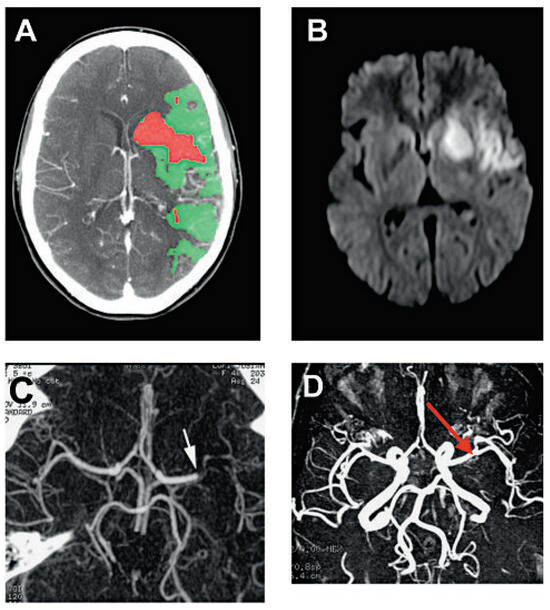

Summary. We report two cases of a 83- and a 78-year-old female with tetralogy of Fallot (TOF) who underwent operation at an advanced age in their 30’s, making them the oldest patients repaired for tetralogy of Fallot [...]